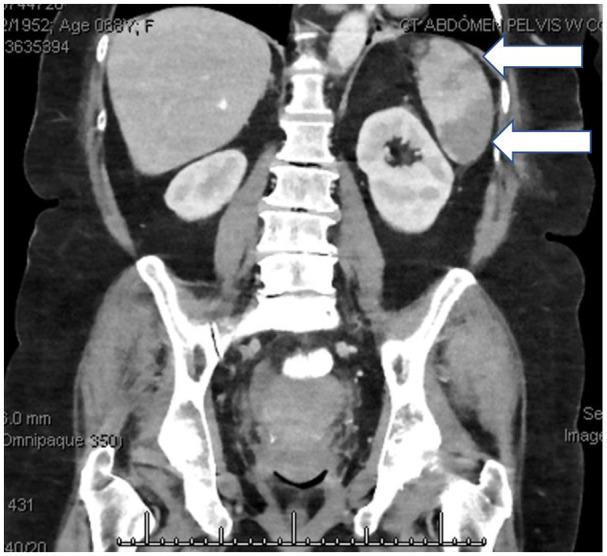

Splenic infarction is an uncommon cause of abdominal pain. In this article, we present a case of isolated splenic infarction presenting with severe abdominal pain, nausea, and with associated generalized weakness. Computed tomography (CT) abdomen and pelvis with contrast revealed multiple splenic infarctions of the entire lower pole with occlusion of the branch splenic arteries, while CT abdomen without contrast was unremarkable. Etiology was later revealed to be thromboembolism secondary to atrial fibrillation. It was managed with anticoagulation. To our knowledge, this is the second case of splenic infarction presenting as an initial manifestation of atrial fibrillation (AF), reported in the literature.

脾梗死是腹痛的一种不常见原因。本文报告了一例以严重腹痛、恶心和全身无力为表现的孤立性脾梗死。腹部和骨盆 CT 增强扫描显示整个下极有多处脾梗死,脾动脉分支闭塞,而腹部 CT 平扫未见异常。病因后来被确定为房颤继发的血栓栓塞。给予抗凝治疗。据我们所知,这是文献中报道的第二个以房颤(AF)首发表现的脾梗死病例。